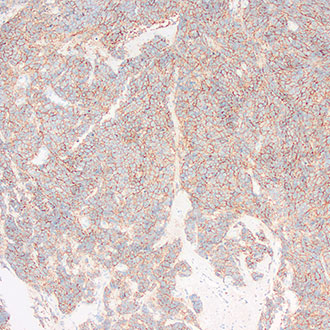

IHC

免疫组织化学(IHC)